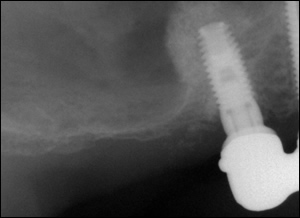

Fig3: Using the Summer's Technique, the floor of the sinus was repositioned "non-surgically". A bone graft and dental implant were placed.